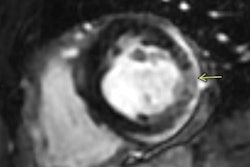

Of these, five athletes (0.6%) ultimately had cardiac MRI findings suggesting inflammatory heart disease (myocarditis in three cases; pericarditis in two cases) that required restriction from play. No adverse cardiac events occurred in athletes who underwent cardiac screening and resumed professional sport participation.